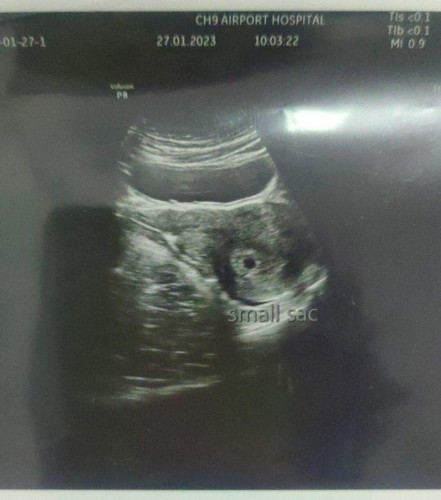

เจอถุงตั้งครรภ์แต่ไม่เจอน้อง

7w4d แล้วค่ะ ถุงตั้งครรภ์เล็กมากแล้วก็ไม่เจอน้อง ตอนนี้กังวนมากเลยค่ะ ท้องแรกด้วย

ของเรา5w2d เจอถุงตั้งครรภ์เล็กๆเหมือนกันค่ะ บางทีแม่อาจจะไข่ตกช้า การนับวีคเลยคาดเคลื่อน ลุ้นไปด้วยกันนะคะ 🤍